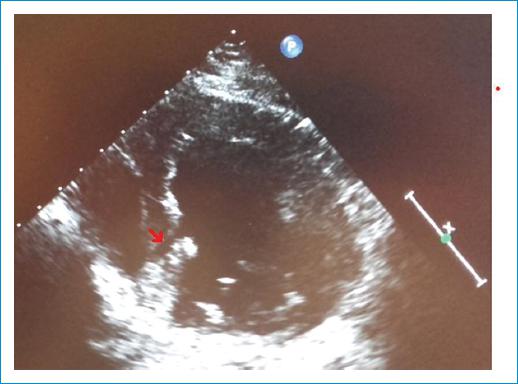

Las hendiduras o criptas miocárdicas pueden presentarse tanto en sujetos sanos como en pacientes con trastornos cardiovasculares. Presentamos el caso de un varón de 61 años, exfumador, que consulta por dolor torácico atípico con test de isquemia no concluyente. Se le realizó una coronariografía que no mostró lesiones en las arterias coronarias. En el ecocardiograma transtorácico se observó una hendidura en el septo inferior basal compatible con hendidura miocárdica (Fig. 1), por lo que se solicitó una resonancia magnética (RM) para completar el estudio. No se observaron alteraciones de la contractilidad en las secuencias de cine-RM ni fibrosis en las secuencias de realce tardío. Se confirma la presencia en la porción basal del septo inferior del diagnóstico de hendidura miocárdica (Fig. 2).

Figura 1 Imagen ecocardiográfica en la que se observa una hendidura digitiforme en el segmento basal del septo inferior (flecha).